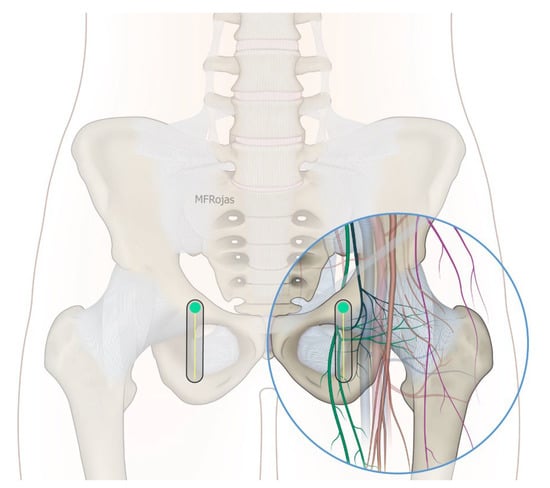

Figure 6. Schematic diagram showing the sagittal plane at the IMA with femoral vessels avoided. Reproduced with permission from Dr Maria Fernanda Rojas Gomez (Bucaramanga, CO). Green dot: transducer mark.

In addition to the classical PENG injection, our modified approach highlighted the addition of pericapsular infiltration in the iliopsoas plane to cover the low articular branch of the femoral nerve and a sagittal approach to target the ONAB. The algorithm was still used to perform diagnostic blocks, followed by alcohol neurolysis 10 min later for those with a positive diagnostic block in the same setting under real-time ultrasound guidance (Philips Affiniti 70, 5–12 MHz linear probe or 1–5 Hz curved probe depending on the depth of the target). In the modified approach, the procedure consisted of 3 needle insertions with the use of 22-gauge 10 cm Quincke needles. The first needle for the high femoral nerve articular branches (high FNAB branches) and AON was inserted in the same way as the PENG approach between the anterior inferior iliac spine (AIIS) and the iliopubic eminence (IPE) deep to the psoas tendon (Figure 2 and Figure 3). A second needle for the low branches of FNAB was inserted in-plane from lateral to medial and advanced through the sartorius, rectus femoris and iliopsoas muscles. The final needle position was in the plane superficial to the iliofemoral ligament medial to the rectus femoris tendon over the femoral head (Figure 4 and Figure 5). The third injection for the obturator nerve articular branches was used to target the caudal aspect of the inferomedial acetabulum (IMA) by scanning in a sagittal plane with a caudal-to-cephalad needle trajectory. The precise localization of the caudal aspect of the IMA could be first approached via the ordinary way (an oblique scan) as described in our first case series [5]. The probe was slowly rotated obliquely until the acetabulum, femoral head, and neck were aligned in the same plane, with the superomedial acetabulum coming into view. The probe was then slid caudally with the end point being the presence of the acetabulum without the femoral head. This referred to the location of the inferomedial acetabulum. The probe was then adjusted until the IMA was in the middle of the image, followed by rotating the probe by approximately 60 degrees (Figure 6). In this scan, the pectineus, the caudal aspect of the IMA and, occasionally, the obturator externus were seen. The ONAB could be visualized in the wedge of the subpectineal space directly adjacent to the IMA. Before any needle insertion, the probe was tilted slightly medially towards the obturator foramen to look for the acetabular/posterior branch of the obturator vessels which are usually deeper than the ONAB. The needle was then inserted from caudal to cephalad in-plane until the needle tip reached the wedge space consisting of the ONAB (Figure 7). In case the wedge space could not be clearly visualized, the needle tip would then be advanced until touching the caudal bony surface of the IMA directly underneath the pectineus. Then, 0.5–1% ropivacaine (4, 3 and 2 mL, respectively) was injected into the above three landmarks. The needles were left in situ during the diagnostic test while their positions were reconfirmed by ultrasound before 100% alcohol was injected into the above targets with volumes in a 1:1 ratio between alcohol and local anaesthetics. A decrease of ≥50% in composite pain score on hip flexion at 45 degrees 10 min after the blocks signified a positive diagnostic block. As a post-neurolysis routine manner, stylets were reinserted before needle withdrawal.

Our modified approach to the ONAB would have the following advantages over the ordinary oblique approach published in our first case series [5]. First, in patients with hip fracture, their fractured limb is commonly externally rotated. This would deviate the femoral vessels to overlay the needle trajectory to the ONAB at the inferomedial acetabulum (Figure 8). This sagittal approach can reliably avoid the femoral vessels in the trajectory. Second, the sagittal scan allows us to visualize the acetabular/posterior branch of the obturator vessels underneath the ONAB, and this can minimize the chance of inadvertent puncture of these small vessels. Third, the ONAB anatomically courses along the caudal aspect of IMA instead of the lateral aspect of IMA [24]. The modified approach can potentially target the ONAB more precisely. Lastly, the modified approach allows the ONAB to be visualized clearly in non-obese patients, whereas the ordinary approach only relies on a rough bony landmark of IMA. Although a large volume of subpectineal injection may lead to a spread to the motor branch of obturator nerve [27], we did not identify any case with neurological deficit along the obturator nerve distribution in our study.